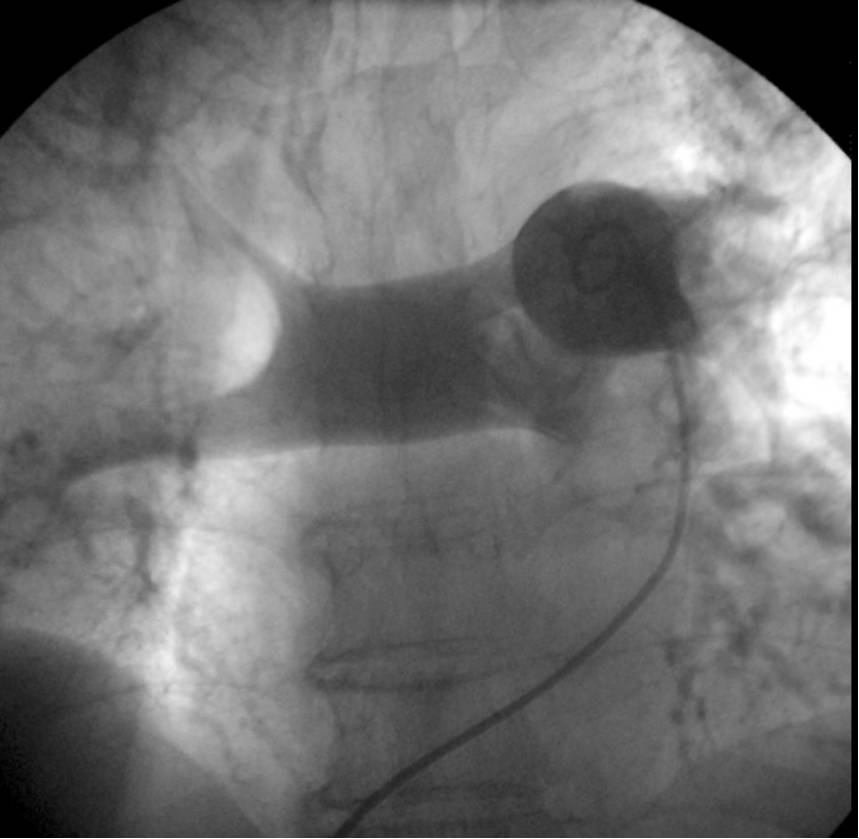

3.介入和手术治疗:存在溶栓禁忌或溶栓失败的高危和中高危血流动力学失代偿患者,可以行外科肺动脉血栓切除术(Ⅱb C),也可以推荐经导管近端肺动脉血栓切除术或碎栓术(Ⅱb B)。

5.肺动脉造影和下肢静脉造影